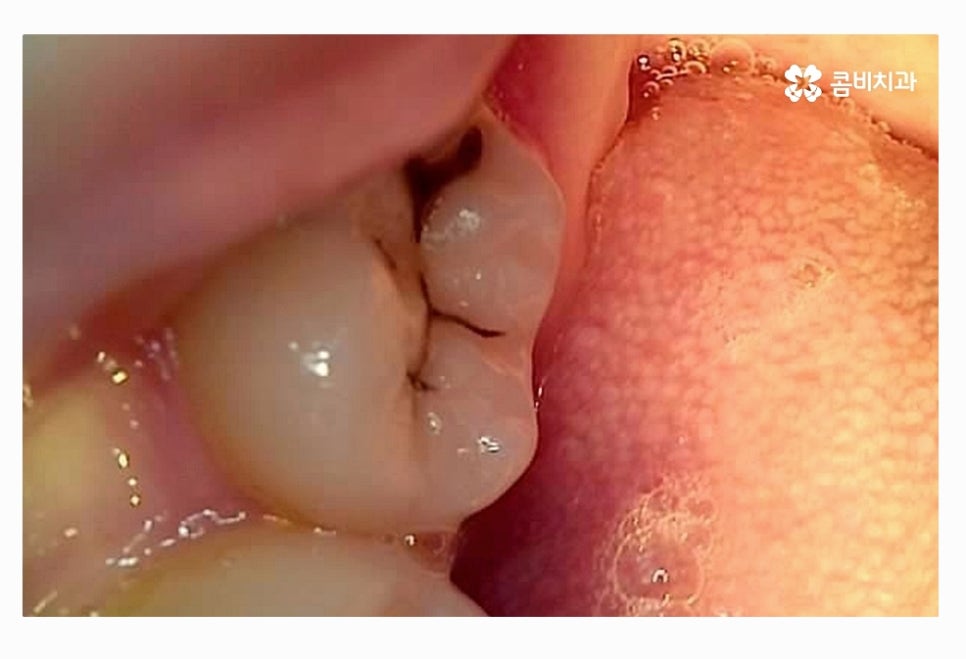

위 사진에서 보시는 것처럼 사랑니가 누워서 자라는 사례는

턱뼈가 좁은 한국인들에게 자주 나타나는 사례이며

음식물이 치아 사이에 끼거나 치석이 쌓이기 쉽기 때문에

청결 관리 미흡으로 인한 구강질환이 발생할 수 있어요.

사랑니가 누워서 자라는 경우에는 청결 관리를 떠나서

어금니 쪽으로 사랑니가 자라면서 주변에 염증을 발생시킬 우려도

있고 턱뼈 손상으로 이어지는 경우도 있기 때문에

사랑니 충치와는 무관하게 발치가 필요할 수 있는데요.

사랑니가 매복이 된 상태에서 위 사진처럼 부분적으로 돌출이 되어

사랑니 충치 심해지는 경우도 많고 주변 잇몸이 붓고

염증이 심해져서 잇몸에도 안 좋은 경우가 많이 있어요.